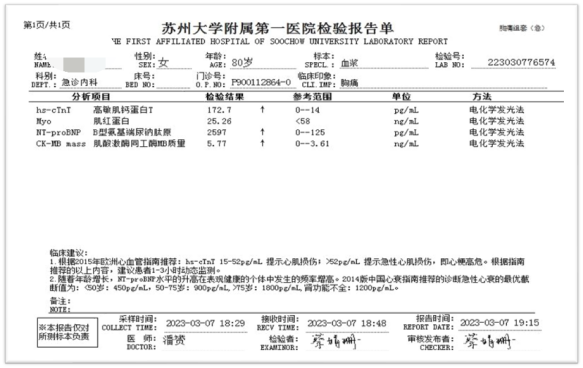

患者急诊心电图提示avR导联ST段抬高0.05mV,I、avL、V3-V6导联ST段压低0.05-0.1mV,心肌酶谱超敏肌钙蛋白T明显升高(大于正常范围上限3倍以上)。